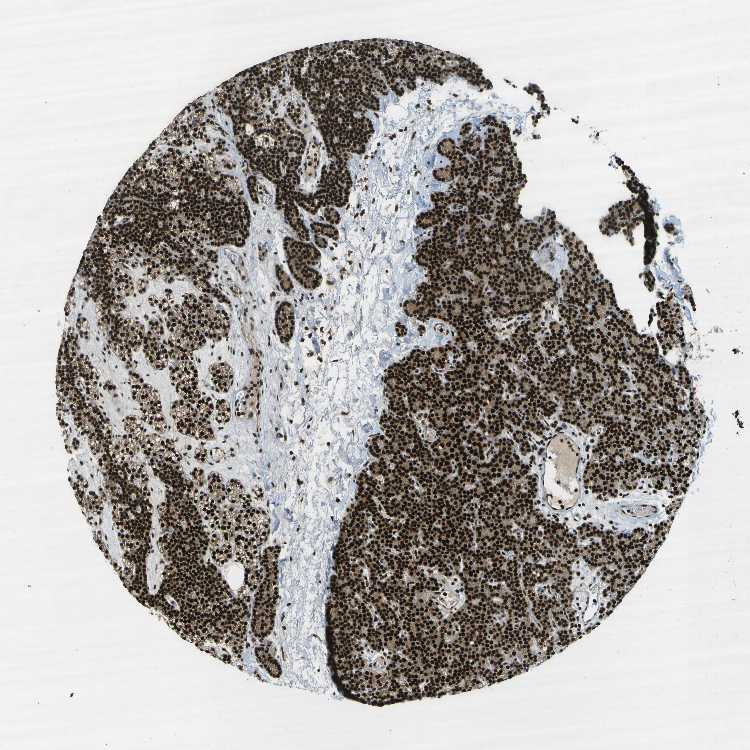

PARATHYROID GLAND - Antibody stainingi

Antibody staining in the annotated cell types in the current human tissue is reported as not detected, low, medium, or high, based on conventional immunohistochemistry profiling in selected tissues. This score is based on the combination of the staining intensity and fraction of stained cells.

Each image is clickable and will lead to virtual microscopy that enables deeper exploration of all samples and also displays staining intensity scores, fraction scores and subcellular localization as well as patient and tissue information for each sample.

Antibody HPA016949

Glandular cells High